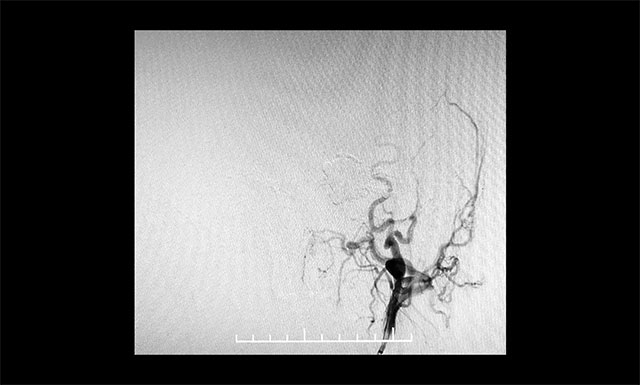

▲ 微导管造影确认后,注入 Onyx 18胶7.5ml